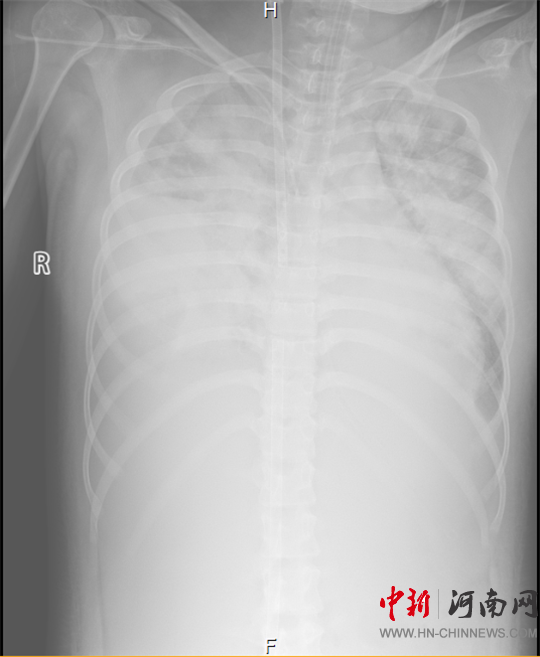

胸部X片顯示

雙側(cè)白肺